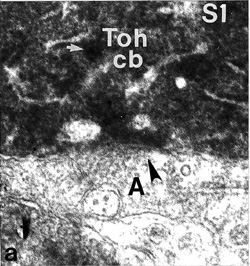

Figure 2: EM of the Toh-IR amacrine cell.

a) An amacrine profile (A) makes a narrow-cleft synapse with small caliber synaptic vesicles (arrowhead) upon the base of the Toh-IR cell body in stratum 1 of the IPL. The Toh-IR cell cytoplasm contains dense-cored vesicles (white arrow).